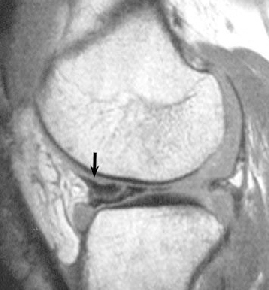

ACL 손상 방사선 사진4